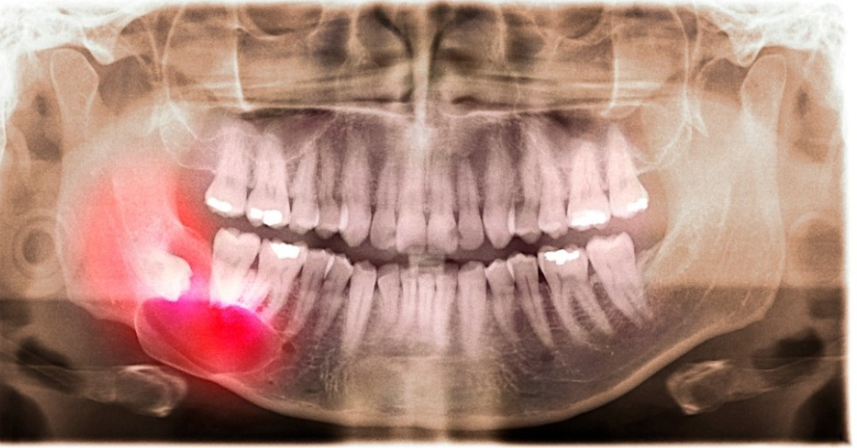

여러 가지 종류가 존재하고 있긴 하나 요즘에는 네비게이션 임플란트라는 방식이 기존에 있던 방식보다 보완된 부분이 있어서 선호되는 분위기였어요. 이전까지는 엑스레이 사진만 보고 식립을 진행하였기에 의료진의 경험이나 기억력이 진료에 많은 영향을 주고 있었어요.

네비게이션 과정은 3D 방식으로 진행이 되는데다 CT 및 구강스캐너로 얻게 된 정보를 참고하여 식립방향, 깊이, 각도와 같은 부분들을 계산할 수 있었어요. 모의술식으로 먼저 계획을 세운 다음에 식립이 진행되어서 기존방식보다 정밀하고 안정성도 나은 부분이 있었어요.